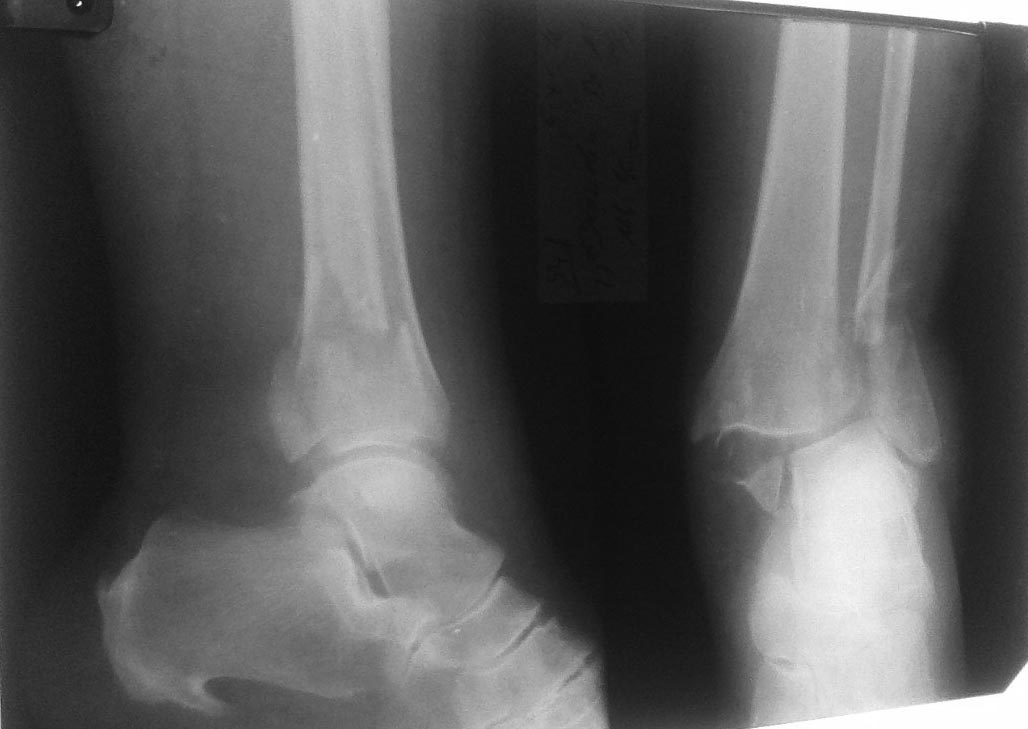

Здравствуйте многоуважаемые коллеги! Хотелось бы обсудить тактику дальнейшего лечения пациентки:Пациентка,70лет.Травма в быту 5.11.16.Д-з:Закрытый перелом обеих лодыжек и заднего края б/берц. кости со смещением отломков.

Из сопутствующих заболеваний СД.Ожирение 3 ст.Ситуация усложняется наличием некроза в обл. медиальной лодыжки.При поступлении наложена система скелетного вытяжения.Назначена протовоотечная терапия

На мой взгляд, речь не о переломе лодыжек, а о переломе пилона и наружной лодыжки. Для КТ прямые показания. И неплохо бы увидеть рентген на вытяжении и фото участка некроза. Один из возможных вариантов лечения - остеосинтез наружной лодыжки, не дожидаясь разрешения ситуации с некрозом. Глубокий некроз сам ведь не заживет. Вполне вероятно, нужна будет активная тактика, в зависимости от глубины наркоза. Если при установке пластины будет достигнута приличная репозиция, можно временно заблокировать голеностопный сустав винтами через нижние отверстия пластины. А 2-3 верхних ввести в большеберцовую выше линии перелома. Появится относительно стабильная ситуация и можно будет спокойнее решать проблему участка некроза. Конечно, с применением съемной подкладочной лонгеты или чего-то подобного, позволяющего легкий доступ к зоне внутренней лодыжки. Можно и внутреннюю лодыжку зафиксировать ретроградно стягивающим винтом. Но это уже будет зависеть от ситуации со всем дистальным концом большеберцовой кости.

В подобной ситуации применял аппаратный остеосинтез по Илизарову. После восстановления оси путем дистракции, проводится спица с напайкой через наружную лодыжку и синдесмоз стягивается. Некроз в области медиальной лодыжки ведется стандартно- некрэктомия после формирования струпа и дней через 7-8- аутодермопластика расщепленным лоскутом.

Alexander Konovalov 10 Ноябрь 2016, 20:30

Хотелось бы увидеть R-граммы и фото ноги.

Вытяжение быстрее поменять на АВФ (устранить грубое смещение). Использование пластин грозит большим риском параимплантной инфекции, что вызовет другие осложнения (флегмоны, остеомиелит и т.д.).

Наружную лодыжку можно отрепонировать закрыто интрамедуллярно фиксацией спицами/стержнем. ДМС фиксировать спицами с напайкой. Медиальную - спицами. Потом R/КТ и думать дальше. Перевязки осуществлять Повидон-йодом.